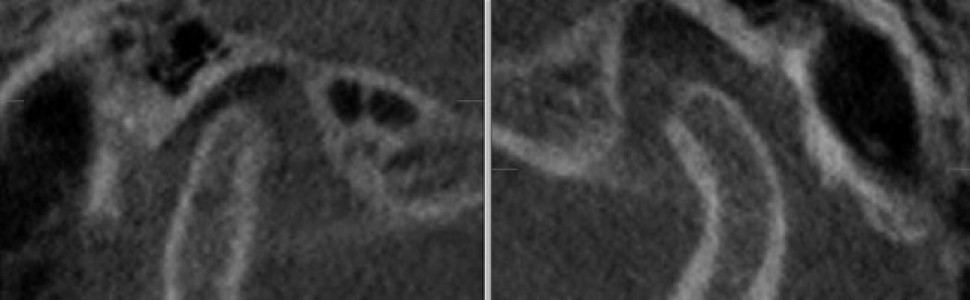

Ryc. 2. Przekroje czołowe ssż. Prawa głowa żuchwy ma kształt wypukły, a lewa jest spłaszczona.

W celu oceny położenia głów żuchwy w ssż oraz wykluczenia zmian morfologicznych narządu żucia wykonano badanie tomografii stożkowej CBCT o dużym polu obrazowania, w zwarciu nawykowym. W badaniu stwierdzono asymetrię ustawienia głów żuchwy w panewkach – prawa głowa żuchwy była ustawiona bardziej dotylnie niż lewa. Z kolei lewa głowa żuchwy była ustawiona centralnie w panewce w płaszczyźnie przednio-tylnej, ale wysunięta do dołu w porównaniu z prawą głową żuchwy (ryc. 1). Na przekrojach czołowych prawa głowa żuchwy miała kształt wypukły, a lewa była spłaszczona, co może wskazywać na zmiany zwyrodnieniowe (ryc. 2). W badaniu CBCT nie stwierdzono obecności zmian zapalnych okołowierzchołkowych, które mogłyby być przyczyną dolegliwości bólowych, jak też zmian zapalnych zatok obocznych nosa.